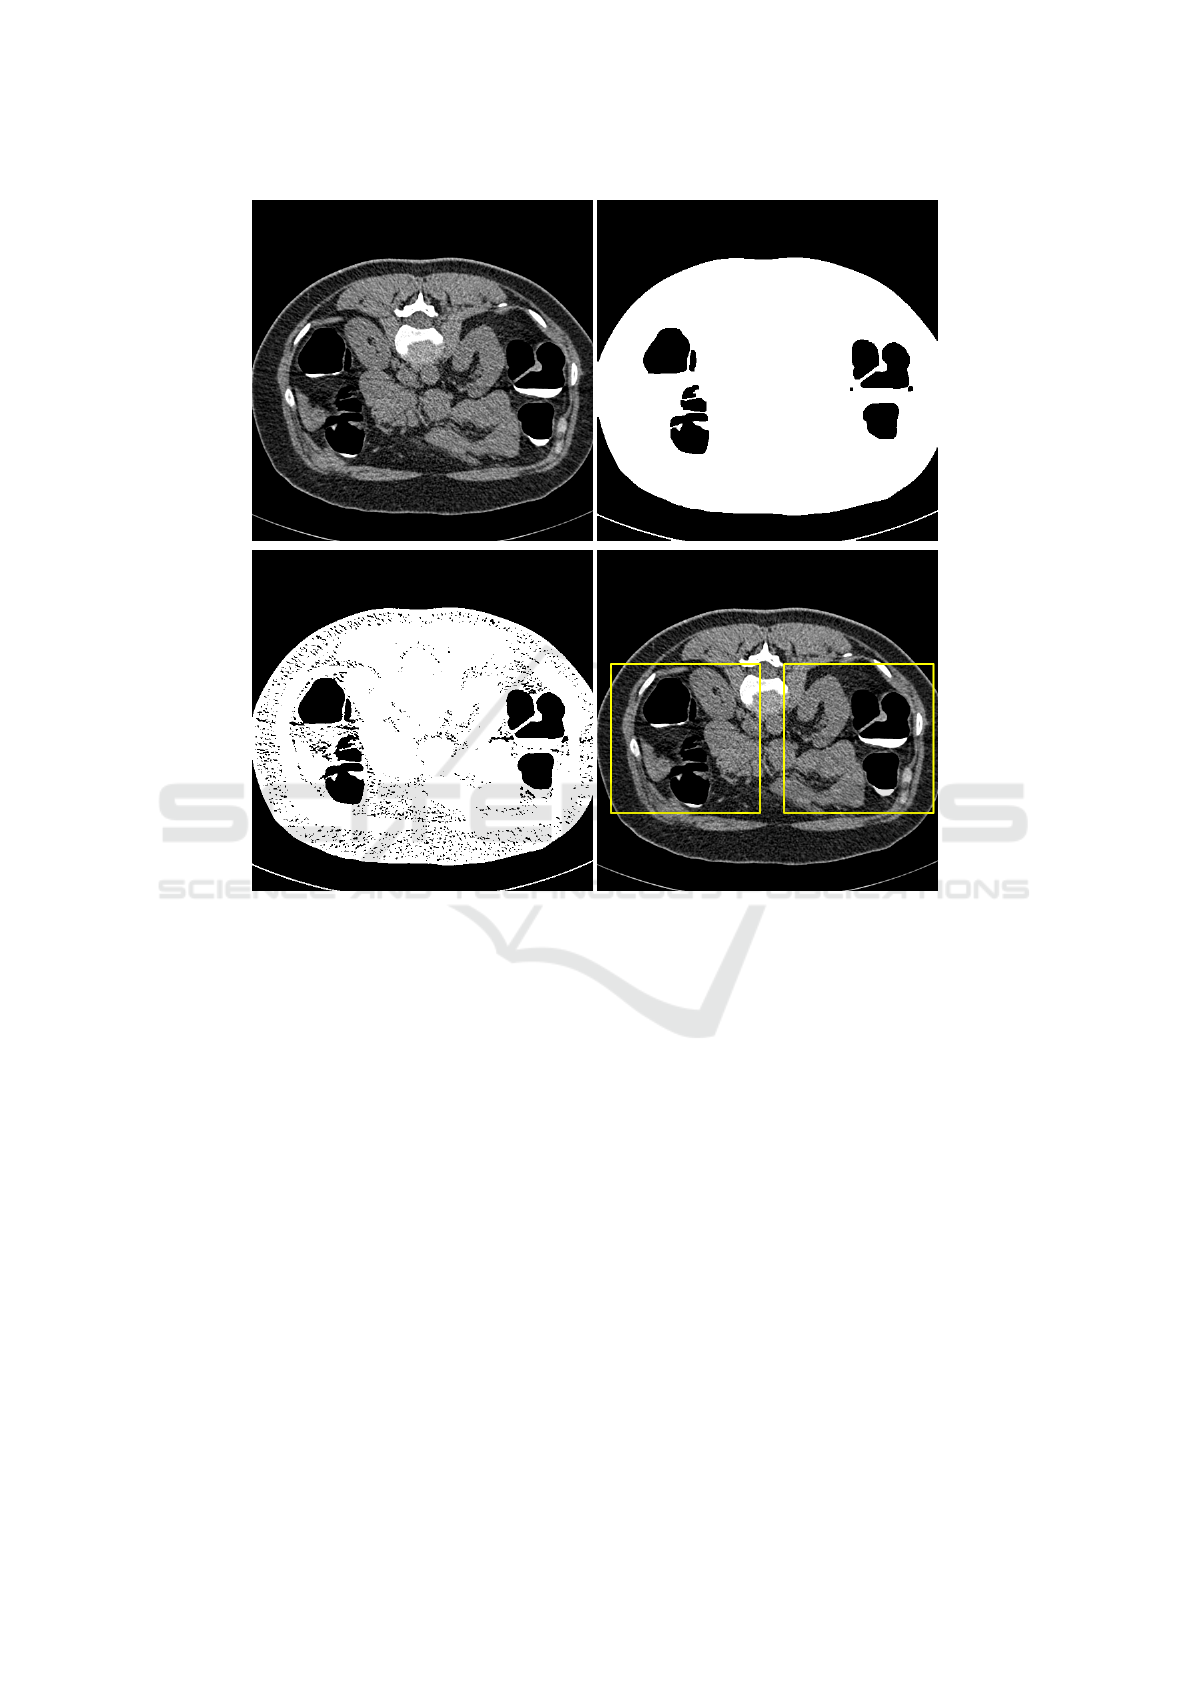

annotation and precise colon segmentation. This paper proposed a method based on multiple instance learning

and transfer learning. Our scheme firstly extracts many small patches from CTC images by using threshold

segmentation method, then a pre-trained model was applied for feature extracting of instances, next pooling

operator was used to aggregating these instance features into a bag, finally, classification result was obtained

by a classifier. Our proposed method does not rely on accurate colon segmentation and the result show that it

can achieve a high accuracy rate.